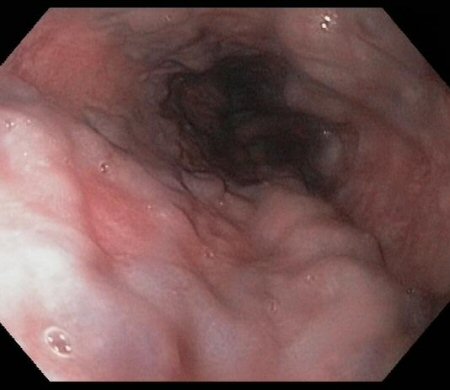

Moderate to severe oesophagitis with multiple linear, clean-based oesophageal ulcers

From the collection of Douglas G. Adler, MD